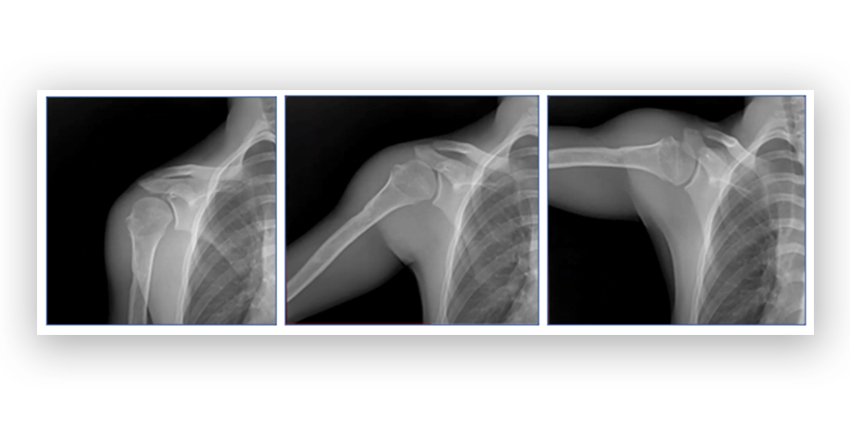

Compared with conventional static imaging, dynamic digital radiography is able to provide a better understanding of shoulder injuries and the outcomes after treatment, Emory Healthcare researchers say.

The Konica Minolta Healthcare Dynamic Digital Radiography is a more nuanced type of X-ray system that can capture motion thus providing more quantitative data on shoulder motion than a standard X-ray system can provide.

During their study, 121 patients had their shoulders analyzed using dynamic digital radiography. In order to assess motion properly, the researchers did scans first with the arm at rest by the patient’s side and then all the way to maximal abduction when the arm is raised away from the body. They gathered data on humeral abduction, scapular upward rotation and scapulohumeral rhythm.

Dynamic digital radiography is not fluoroscopy. It provides both static and dynamic images at high speed and low dose, allowing the physician to visual how the anatomical structures of the shoulder interact and change over time, the researchers explained.